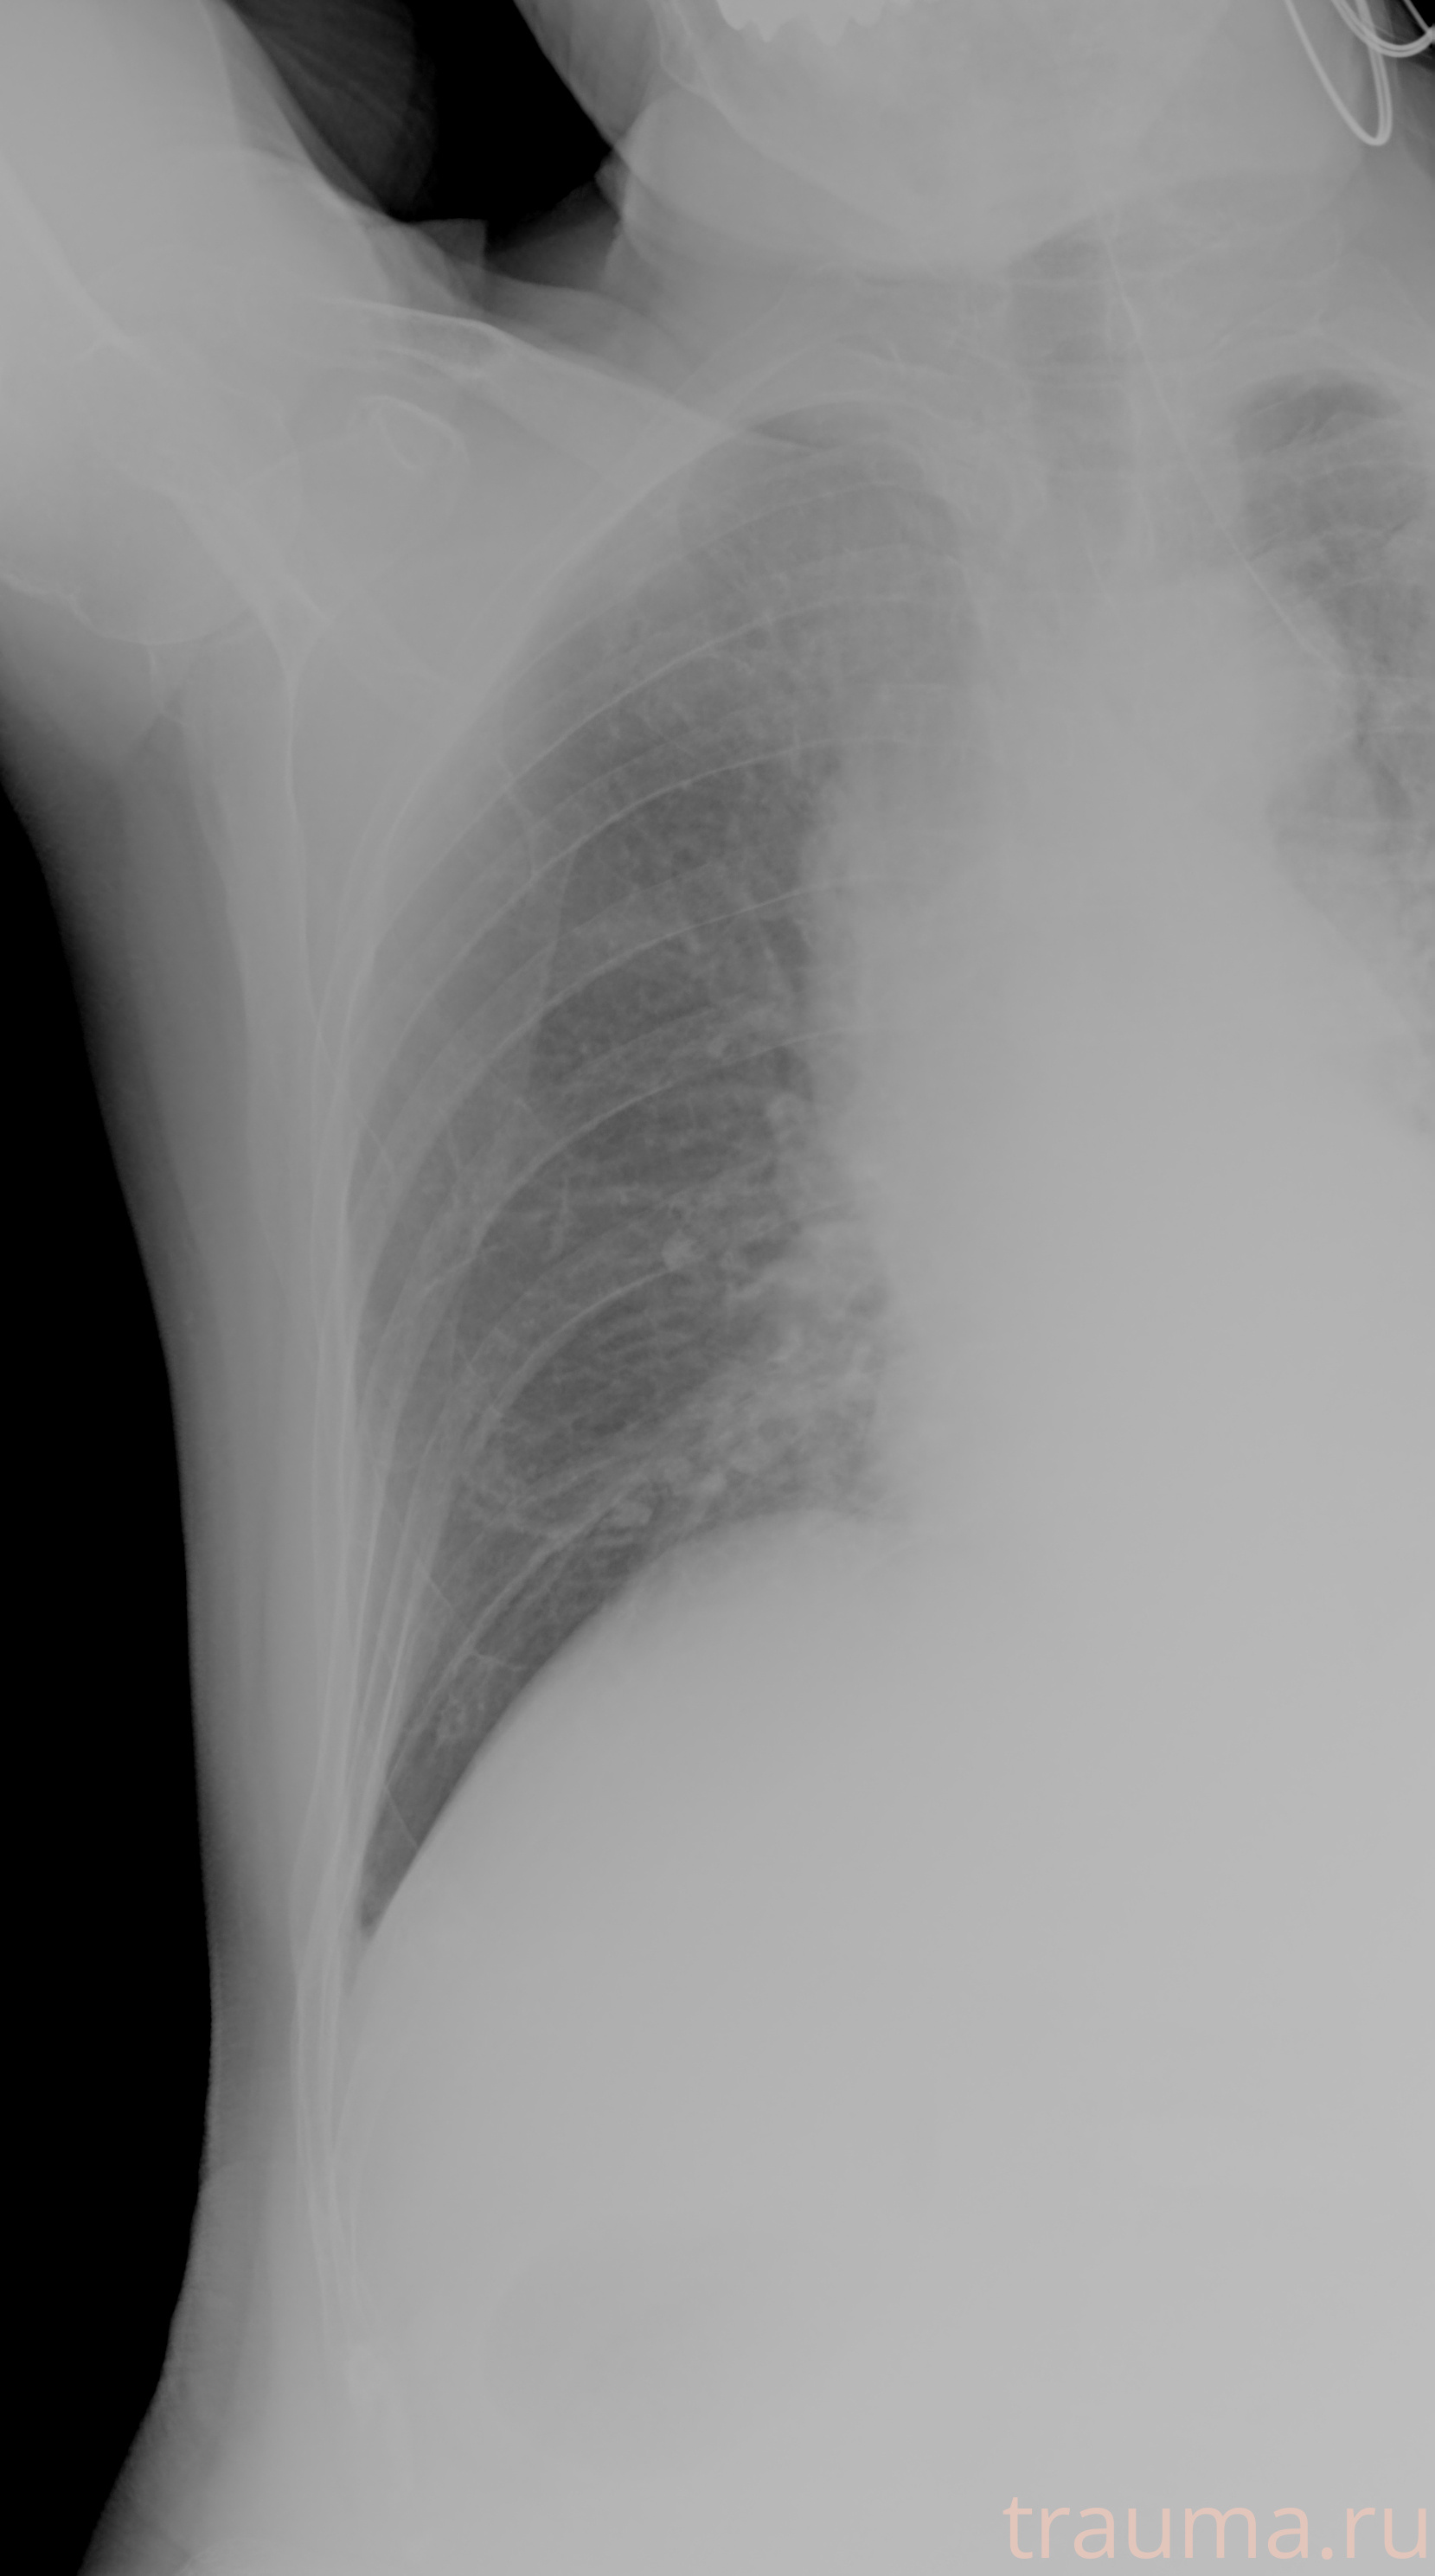

Рентген на дому: по вашему адресу приезжает врач-рентгенолог, травматолог-ортопед с мобильным рентгеновским аппаратом, проводит диагностику травмы или заболевания, делает необходимые рентгенограммы, дает рекомендации по дальнейшему лечению. Получить качественные снимки в домашних условиях возможно благодаря уникальной методике, разработанной МосРентген Центром для института  Склифосовского